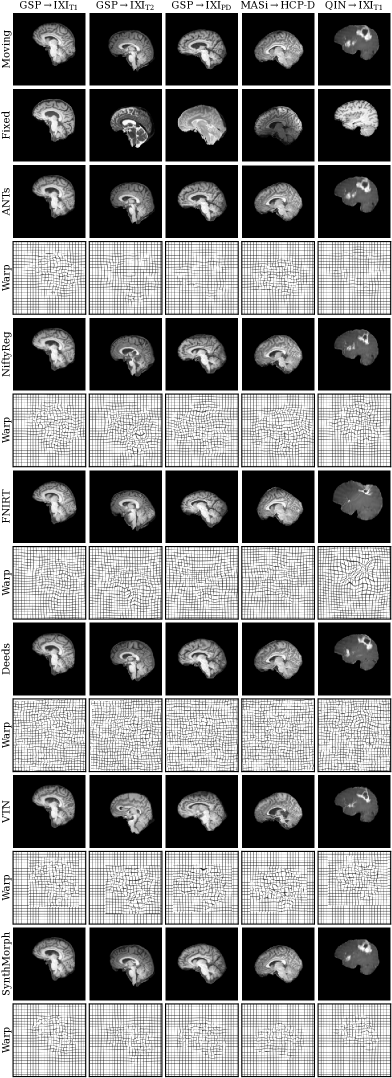

4.6.2 Results

Figure 13 shows typical deformable registration examples for each method, and Figure 14 quantitatively compares registration accuracy across testsets in terms of mean Dice overlap over the 21 largest anatomical structures (large-21), 10 fine-grained structures (small-10) not optimized at training, and image similarity measured with NCC-MIND. Supplemental Figures S.1–S.5 show deformable registration accuracy across individual brain structures.

Although SynthMorph trains with synthetic images only, it achieves the highest large-21 score for every skull-stripped testset. For all cross-contrast pairings and the pediatric testset, SynthMorph leads by at least 1.7 Dice points compared to the highest baseline score (MASiHCP-D, for paired two-sided -test) and often much more. Across these testsets, SynthMorph performance remains largely invariant, whereas the other methods except Deeds struggle. Crucially, the distribution of SynthMorph scores for isotropic data is substantially narrower than the baseline scores, indicating the absence of gross inaccuracies such as pairs with that several baselines yield across all isotropic contrast pairings. On the clinical testset QINIXIT1, SynthMorph surpasses the baselines by at least . For GSPIXIT1, it outperforms the best classical baseline ANTs by 1 Dice point ().

Across the T1w testsets, FNIRT outperforms NiftyReg by several Dice points and also ANTs for MASiHCP-D pairs. Surprisingly, FNIRT beats NiftyReg’s NMI implementation for GSPIXIT2, even though FNIRT’s cost function targets within-contrast registration. The most robust baseline is Deeds, which ranks third at adult T1w registration. Its performance reduces the least for the cross-contrast and clinical testsets, where it achieves the highest Dice overlap after SynthMorph.

The only joint DL baseline with trained weights that we had access to, VTN, yields relatively low accuracy across all testsets. This was expected for the cross-contrast pairings, since the model was trained with T1w data, confirming the data dependency introduced with standard training. However, VTN lags behind the worst-performing classical baseline for GSPIXIT1 data, NiftyReg, too (, ), likely due to domain shift as in the affine case.

Considering the fine-grained small-10 brain structures held out at training, SynthMorph consistently ranks among the two best-performing methods, matching the performance of Deeds for GSPIXIT1 (, ) and GSPIXIPD (, ), and leading by at least () on the clinical testset.

Interestingly, SynthMorph outperforms all baselines across testsets in terms of NCC-MIND (), although it is the only method not optimizing or trained with an image-based loss.

Figure 15 shows the relative change in large-21 Dice for each tool when run end-to-end compared to affine initialization with NiftyReg. SynthMorph’s drop in performance is 0.05% or less across all datasets. For GSPIXIT1, classical-baseline accuracy decreases by no more than . Across the other datasets, the classical methods generally cannot make up for the discrepancy between their own and NiftyReg’s affine transform: accuracy drops by up to , whereas SynthMorph remains robust. The performance of VTN reduces by at least across testsets and often much more, highlighting the detrimental effect an inaccurate affine transform can have on the subsequent deformable step. Figure 12 shows the importance of skull-stripping for deformable registration accuracy. Generally, deformable accuracy suffers less than affine registration when switching to full-head images, as these algorithms can deform different image regions independently. SynthMorph remains most robust to the change in preprocessing; its large-21 Dice overlap reduces by less than 0.05%. With a drop of 0.08%, Deeds is similarly robust. In contrast, FNIRT’s performance is most affected and reduces by 5%—a decline of the same order as for most affine methods.

Figure 16 analyzes SynthMorph warp smoothness. As expected, image-based NCC-MIND and large-21 Dice accuracy peak for weak regularization of . In contrast, overlap of the small-10 regions not optimized at training benefits from smoother warps, with an optimum at . The fields predicted by SynthMorph achieve the lowest log-Jacobian spread across all baselines for and are thus closest to the ideal value 1. Similarly, the proportion of folding voxels decreases with higher and drops to at (10 integration steps). Deeds is the weakest-regularized method and yields folding voxels, whereas the other baselines achieve . For realistic warp fields with characteristics that match or exceed the tested baselines, we conduct all comparisons in this study with a default weight . We highlight that is an input to SynthMorph, enabling users to choose the optimal regularization strength for their specific data without retraining.

Deformable registration with SynthMorph is highly symmetric (Figure 11), with a forward-backward inconsistency of only of the voxel size, that closely follows ANTs (0.2%) and NiftyReg (0.5%). In contrast, the other methods have inconsistencies of the order of the voxel size.

Figure 10(b) assesses the dependency of registration performance on slice thickness . Similar to the affine case, deformable accuracy decreases for thicker slices, albeit faster. SynthMorph performs most robustly. Its accuracy remains unchanged up to mm and reduces 95% at mm. ANTs is the most robust classical method, but its accuracy drops considerably faster than SynthMorph. FLIRT and NiftyReg are most affected at reduced resolution, performing at less than 95% accuracy for mm and , respectively.